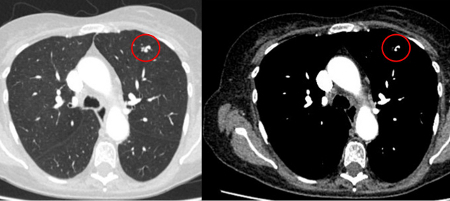

Cortes de tomografia computadorizada (TC) de dois casos com nódulos perifissurais benignos. Observe as margens lisas e a fissura adjacente normal e intacta

Do acervo de Dr. George Tsaknis, MD, PhD, FRCP (Londres), MRQA, MAcadMEd, PGCert; usado com permissão